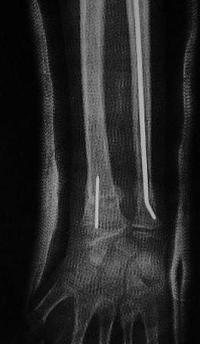

Métaphyse poignet -1 Radio initiale Face

Radio initiale : déplacement en valgus + chevauchement